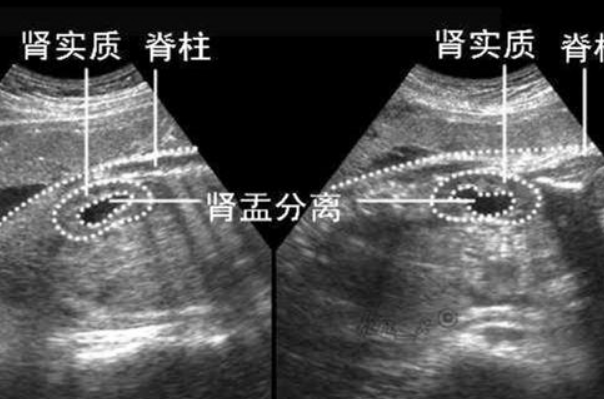

胎儿肾盂分离是指孕妇怀孕20~24周时,利用B超检查发现肾盂的宽度大于4毫米的异常情况,这也可能是是因为肾盂当中有积水的情况,平均100个胎儿中,可能大约会有4-7个胎儿是属于肾盂分离症状的,导致这种症状的因素有很多,其中就包括了下面三种情况:

总之,B超检查时发现胎儿双肾分离的情况,主要是由于羊水过多或尿路感染等因素所导致,不过只要双肾分离在10毫米以内,一般都属于正常生理现象,对胎儿没有影响,此时,孕妇无需过度担忧,只需定期进行产检,密切关注胎儿状况即可。